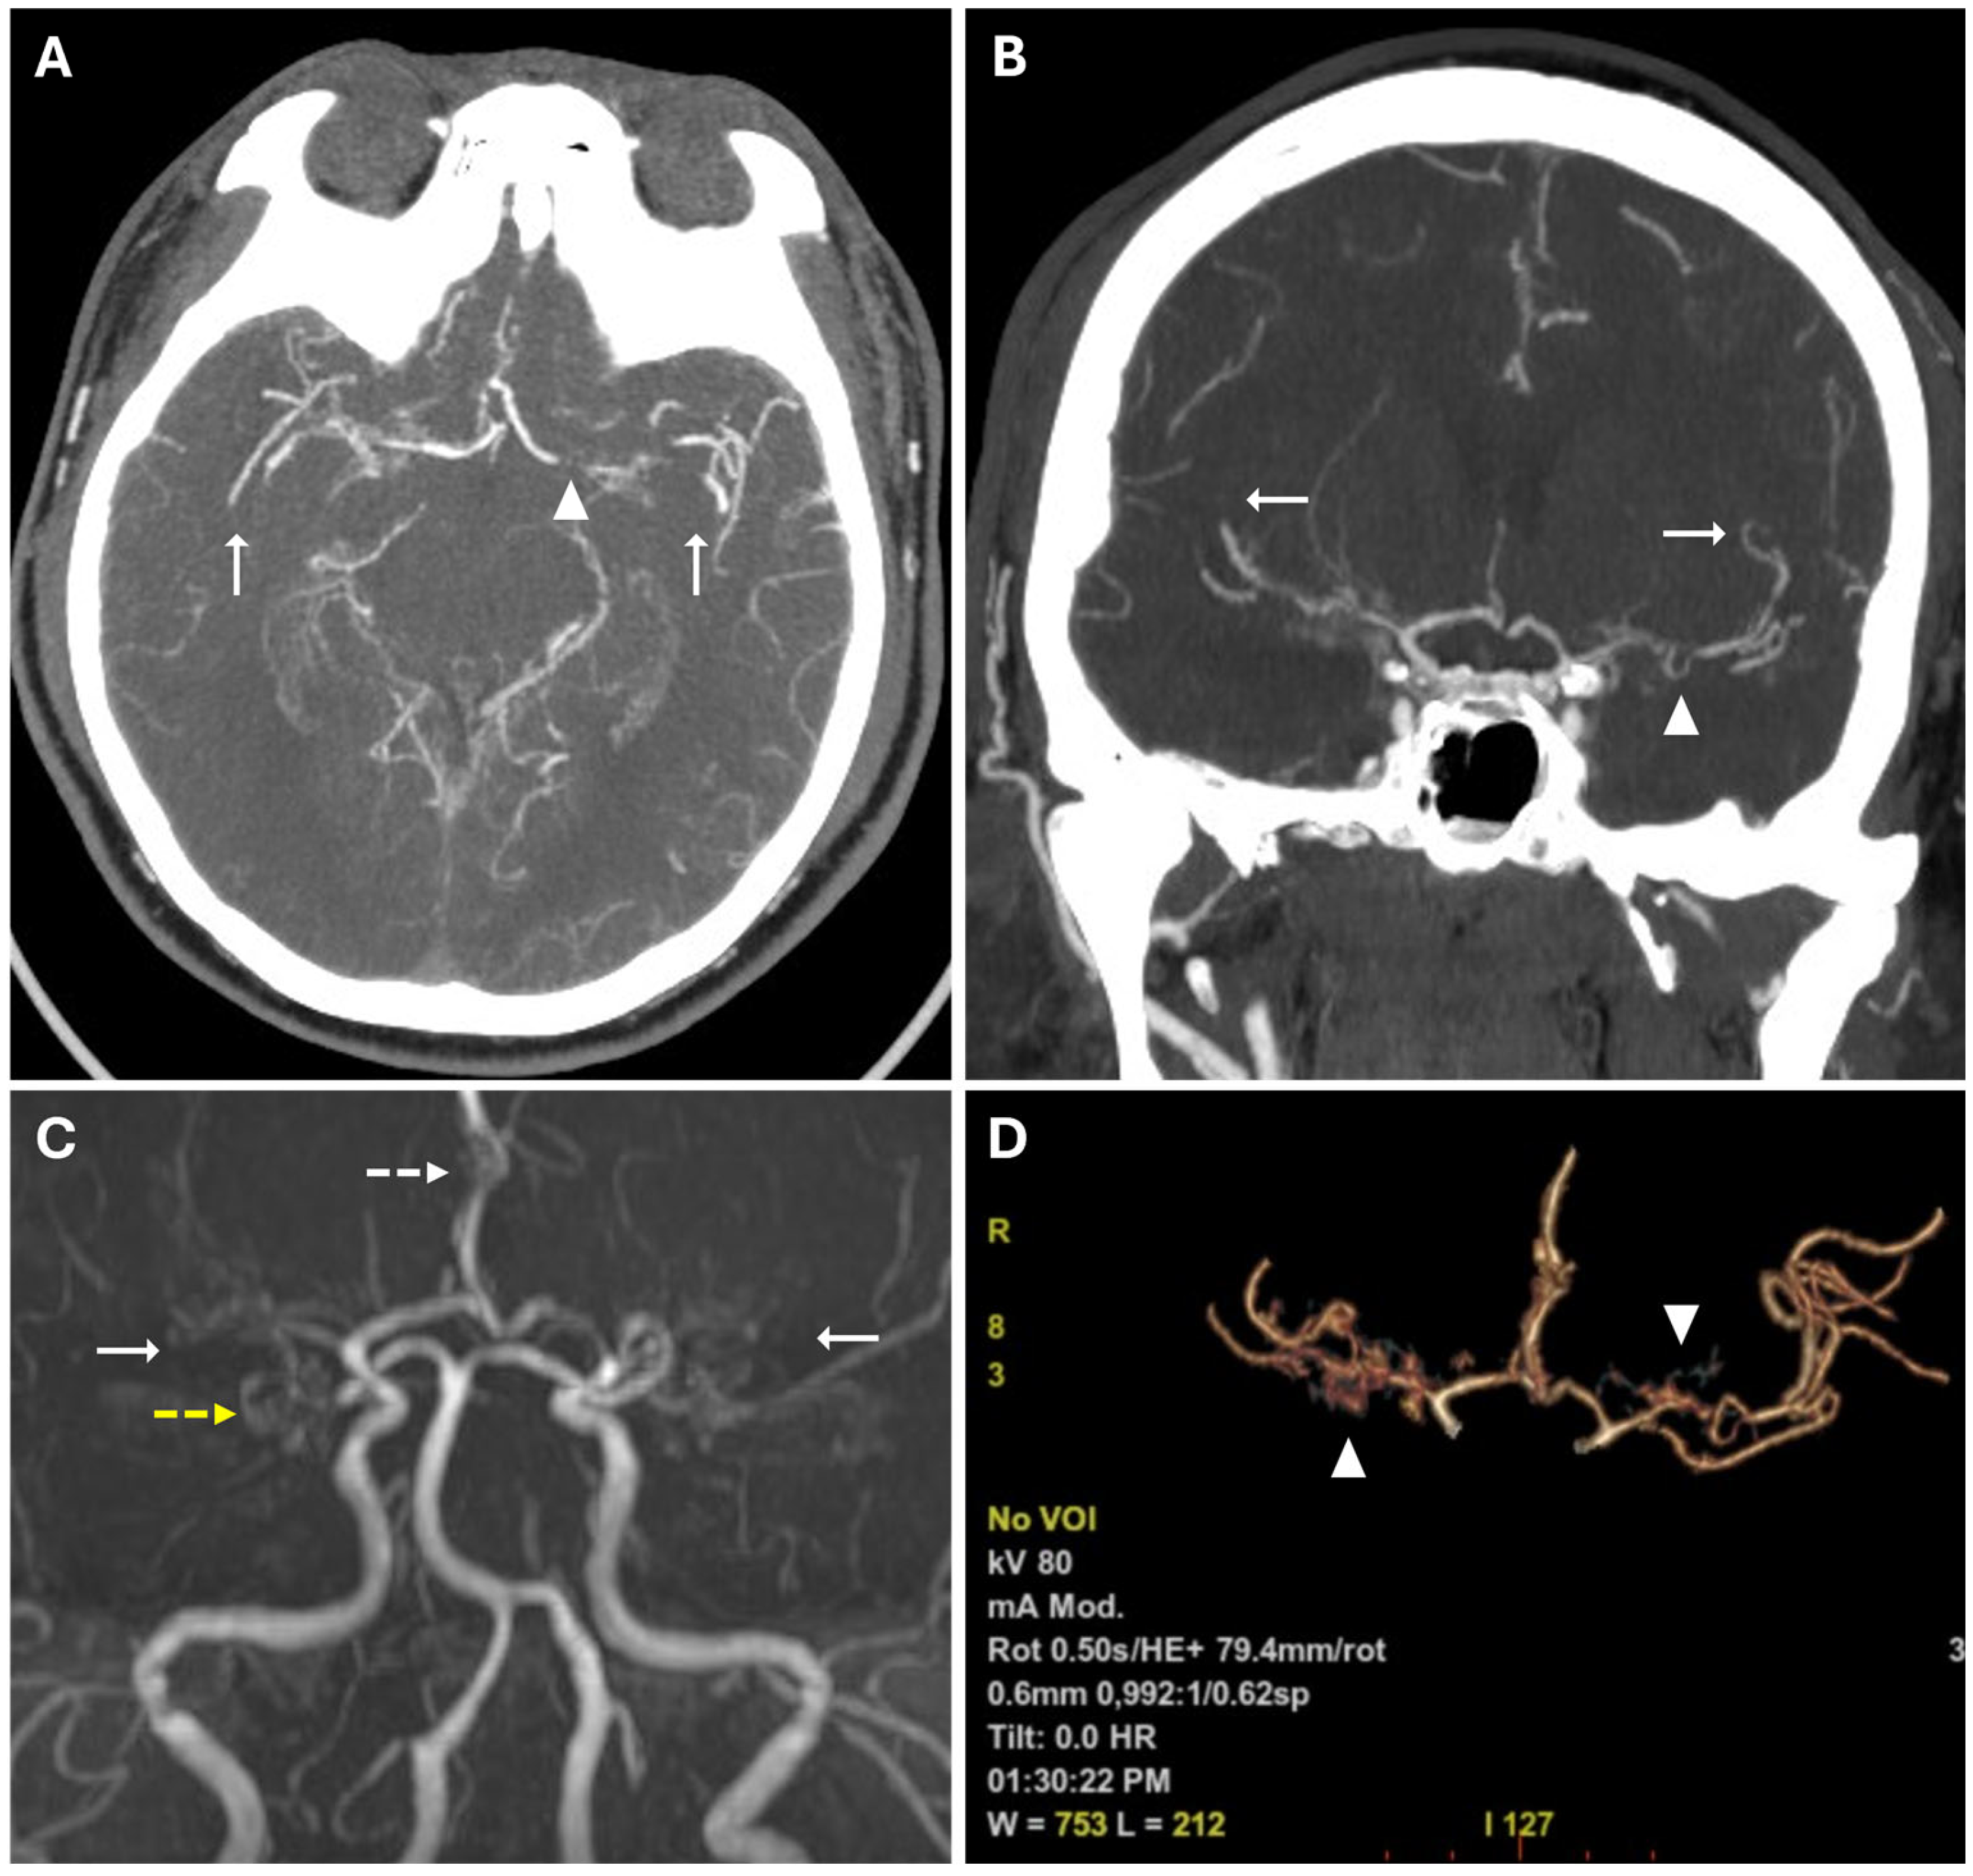

These findings suggested acute ischemic lesions in the right middle cerebral artery territory. There were no hemorrhagic lesions or mass effect on the encephalic parenchyma. Computed tomography angiography (CTA) examination showed reduced caliber and parietal irregularity of M1–M2 tracts of the middle cerebral artery bilaterally, with steno-occlusive tract-like changes. Additionally, vascular ectasia of deep lenticular arteries and the right anterior cerebral artery were also detected (Figure 2).

MRA confirmed the reduced caliber and wall irregularities with steno-occlusive changes in M1–M2 tracts of the middle cerebral artery bilaterally, predominantly on the right. The A2 segment of the right anterior cerebral artery (ACA) and the P2 segment of the right posterior cerebral artery (PCA) also showed irregular caliber due to alternations of stenotic and dilated tracts (Figure 2).

Figure 2. (A,B) CTA images in axial (A) and coronal (B) views, using a Maximum Intensity Projection (MIP) reconstruction, show reduced caliber and parietal irregularity of the M1-M2 tract bilaterally (white arrows) with severe stenotic tract in the left MCA (white arrowheads). (C) 3d MRA sequence shows multiple steno-occlusive changes in M1-M2 bilaterally (white arrows), irregular caliber of the right ACA (white dotted arrows), and right PCA (yellow dotted arrows). (D) Volume rendering reconstruction of CTA shows abnormal collateral perforators (white arrowheads).